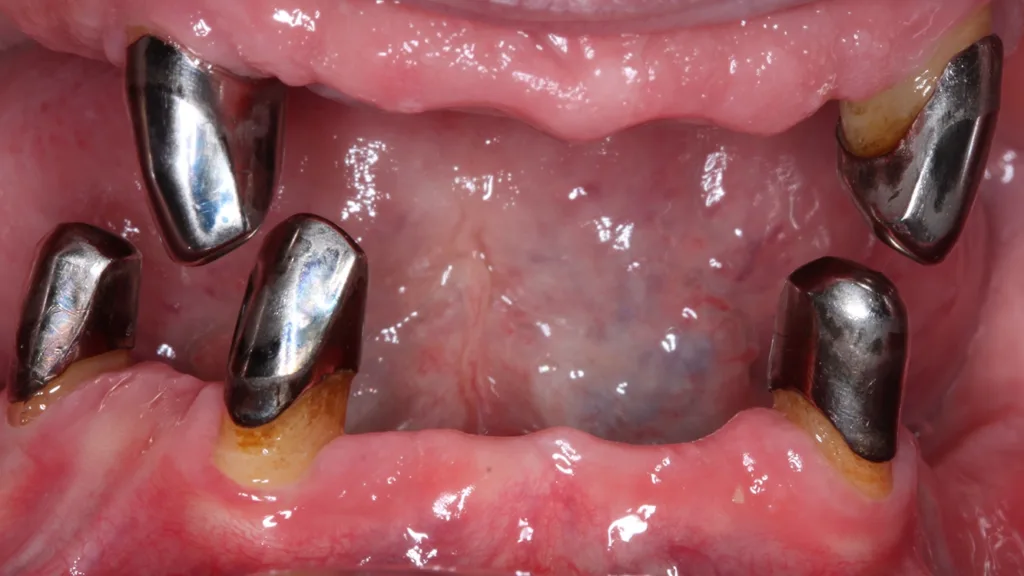

Abb. 3 a–e: Klinische Dokumentation eines 63-jahrigen männlichen Patienten (geb. 05.09.1961). Die Fotodokumentation erfolgte erst am Tag der AIT und nicht im Rahmen der klinischen und radiologischen und 47 wurden vor der AIT entfernt. An den Zahnen 13 und 23 war neben der peniblen subgingivalen Instrumentierung die Applikation von Straumann® Emdogain® (Straumann Group, Basel, Schweiz) vorgesehen.Walter

Abb. 3 a–e: Klinische Dokumentation eines 63-jahrigen männlichen Patienten (geb. 05.09.1961). Die Fotodokumentation erfolgte erst am Tag der AIT und nicht im Rahmen der klinischen und radiologischen und 47 wurden vor der AIT entfernt. An den Zahnen 13 und 23 war neben der peniblen subgingivalen Instrumentierung die Applikation von Straumann® Emdogain® (Straumann Group, Basel, Schweiz) vorgesehen.

Es handelt sich hierbei um einen 63-jährigen männlichen Patienten (geb. 05.09.1961). Allgemeinmedizinisch war eine rheumatoide Erkrankung und die Einnahme von Methotrexat (Folsäureantagonist, Zytostatikum und Immunsuppressivum) dokumentiert. Etwaige orale Nebenwirkungen dieser Medikation lagen nicht vor. Herr B. war Nichtraucher. Der Patient wünschte maximalen Zahnerhalt und wurde daher zur parodontalen Therapie der bereits weit fortgeschrittenen Parodontitis an eine spezialisierte Praxis überwiesen. Zu diesem Zeitpunkt waren im Oberkiefer noch 2 und im Unterkiefer noch 5 Zähne vorhanden.

Der parodontale Screening-Index (PSI) an den verbliebenen Zähnen zeigte erhöhte Zahnlockerungen, stark entzündete und blutende Areale sowie Sondierungstiefen weit über 5 mm hinaus. Es lag dem zufolge ein Code 4* und damit die Notwendigkeit gründlicher Diagnostik vor. Die weiterführenden parodontalen Untersuchungen führten zur Diagnose einer generalisierten Parodontitis Stadium IV Grad C [46]. Die parodontal entzündete Wundfläche betrug 1088,69 mm2 [47]. Radiologisch konnten neben dem generalisierten horizontalen Knochenverlust auch ausgeprägte vertikale Defekte z.B. an den Zähnen 13 und 23 detektiert werden. Darüber hinaus wurde ein Chairside Vitamin-D-Test durchgeführt (Botiss, Straumann Group, Basel, Schweiz). Der Wert betrug 10 ng/ml und bedeutete, dass hier ein schwerer Vitamin-D-Mangel mit entsprechenden Implikationen für den Knochenstoffwechsel vorlag. Dem Patienten wurde eine Vitamin-D-Supplementierung mit zunächst 2000 IE und die Vorstellung bei seinem Hausarzt zu etwaiger weiterer Diagnostik und Festlegung einer optimierten Vitamin-D-Nahrungsergänzung empfohlen [48].

Der Patient wurde über die Krankheitsentstehung, die Prognosen der Einzelzähne und die therapeutischen Optionen aufgeklärt. Es wurde eine systematische parodontale Therapie unter Berücksichtigung der aktuellen EFP/ DGParo-Leitlinien geplant [48]. Der radiologisch sichtbare Knochenverlust an den Zähnen 37 und 47 ging bereits weit über den Apex hinaus. Eine parodontale Therapie erschien daher nicht mehr erfolgversprechend. Die Zähne wurden vor der antiinfektiösen Therapie (AIT) extrahiert und die Alveolen mit adaptierenden Nähten stabilisiert. Im Rahmen der Unterweisungen für eine optimierte häusliche Mundhygiene wurde dem Patienten die Benutzung einer Monobüschelbürste demonstriert und empfohlen. Bei regelmäßiger Anwendung an den vereinzelten, mit Primärteleskopen versorgten Zähnen lassen sich auch diese Zähne in ihrer gesamten Zirkumferenz sehr gut reinigen. Bei den verbliebenen 5 Zähnen war geplant, die zur Verfügung stehenden nichtchirurgischen Möglichkeiten auszuschöpfen. Eine adjuvante Gabe von systemischen Antibiotika war allerdings nicht vorgesehen. Das bedeutete aber, dass im Oberkiefer an den besonders schwer vorgeschädigten Zähnen 13 und 23 neben der subgingivalen Instrumentierung mit Ultraschall und Pulverwasserstrahl (EMS, Nyon, Schweiz) zusätzlich SMP (Straumann® Emdogain®, Basel, Schweiz) appliziert werden sollten [50]. Da beide Zähne einen erhöhten Lockerungsgrad aufwiesen, bestünde die Notwendigkeit einer präoperativen Schienung spätestens vor einer möglichen chirurgischen Stufe-3-Therapie.

Der Punkt, dass beide Zähne demzufolge wohl eher nicht unter optimalen Bedingungen parodontalchirurgisch operiert werden können, hat daher auch zu der Entscheidung einer SMP/EMD-Anwendung in der AIT beigetragen. Die AIT wurde an einem Termin durchgeführt. Nach der Applikation einer Lokalanästhesie wurden alle Zähne zunächst mit Ultraschall und nach Detektion glatter und harter Wurzeloberflächen mit einem erythritolhaltigen Pulverwasserstrahlgemisch mit dem Standard-Handstück behandelt (EMS, Nyon, Schweiz). An den Zähnen 13 und 23 wurden in derselben Sitzung noch zusätzlich SMP – entsprechend einem von Prof. A. Kašaj publiziertem Protokoll (Abb. 5) – appliziert. Zuvor wurde eine Blutstillung unter Verwendung von H2O2 und dem Einbringen von sterilisiertem Superfloss vorgenommen und ein EDTA-Gel zur Konditionierung der Wurzeloberfläche appliziert. Das Aufbringen von Histoacryl® (B. Braun, Tuttlingen, Deutschland) Gewebekleber zum Verschluss der instrumentierten parodontalen „Taschen“ rundete diesen Behandlungszyklus ab. Das detaillierte Vorgehen bei diesem Patienten ist in den Abbildungen 4a–j dargestellt. Da die Zähne nicht geschient werden konnten, wurde der Patient instruiert, auf ein Herausnehmen und Wiedereinsetzen der Prothese sofern möglich in den nächsten Tagen zu verzichten. Nach der AIT wurde die supragingivale Plaquekontrolle an 3 Terminen kontrolliert und die Wundheilung durch professionelle Zahnreinigungen unterstützt.